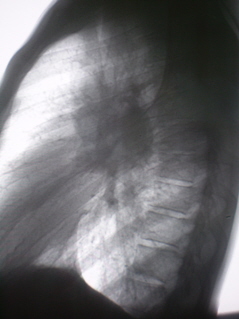

Цифровое стандартное флюорографическое профилактическое исследование (проведено на цифровом флюорографе «Ренекс – Флюоро»). На цифровых флюорограммах, произведенных в прямой, правой и левой боковых проекциях с обеих сторон определяется синдром двусторонней аденопатии. С обеих сторон определяется резкое увеличение и гомгенизация тени корней за счет резко гиперплазированных, в основном, бронхопульмональных лимфатических узлов с довольно чёткими, ровными контурами. Структура тени однородная. На фоне гиперплазированных лимфатических узлов чётко дифференцируются просветы главных бронхов.

Иллюстрации 1, 2, 3.